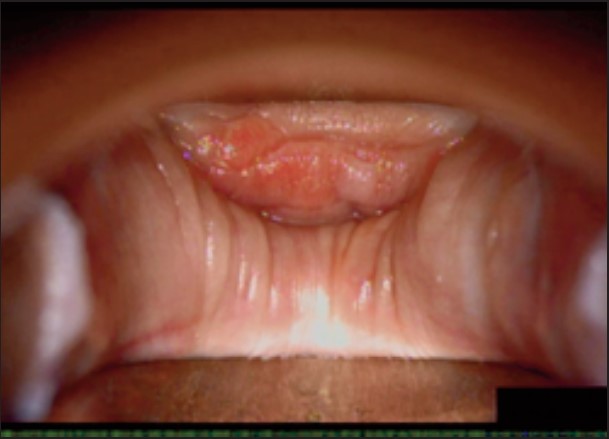

Під час спостереження до та після процедури, через 16 і 36 діб було зроблено вагінальні фотографії за допомогою Tele-Cervico (цервікографія) та виконано порівняння результатів до /після.

У пацієнток 1, 2 і 3 вагінальні складки утворилися та увиразнилися помітніше та сильніше, ніж вони були до лікування, ми оцінили цей клінічний результат після 1-го сеансу (через 16 діб). На нашу думку, такі виразні складки свідчать про підтяжку слизової оболонки піхви, що добре впливає на ущільнення піхви та проблему нетримання сечі. Через 36 діб після процедури ми спостерігали, що зруйнована анатомічна структура піхви відновила Н-подібну форму, тобто стала набагато здоровішою. Зокрема, у пацієнтки 4 структура піхви була цілковито зруйнована, стінки піхви обвисали через втрату еластичності. Однак через 36 днів після процедури структура піхви повністю відновила здорову Н-подібну форму [Див. Малюнок 3].

Пацієнтка №3

До

Після 16 діб

Після 36 діб

| Результати | √ Відновлено H-подібну структуру √ Дещо зменшилися симптоми SUI √ Зросло задовлення партнера √ Зросло задоволення пацієнтки |